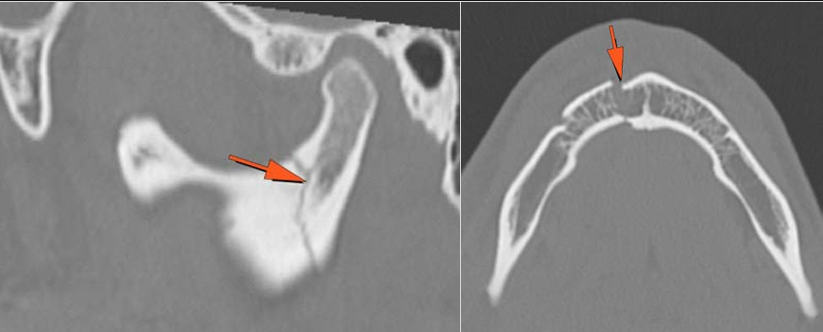

The condylar head and fossa as well as the temporomandibular joint space are fractured and/or dislocated. [Yes/No]

There is condylar fracture either within or outside of the joint capsule, or with or without involvement of the articular surface of the condylar head. [Yes/No]

There is evidence of radiodense intra-articular osteochondral fragments. [Yes/No]

There is bony injury or displacement of the external auditory canal and/or other evidence of temporal bone injury. [Yes/No]